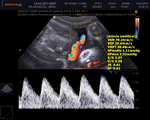

El ultrasonido como parámetro pronostico gestacional, ha revolucionado la obstetricia, aprenderás a realizar los estudios hemodinámicos fetales. Ecocardiografía fetal, Neurosonografía y los diferentes tamizajes. |

El uso de parámetros internacional para la emisión del estatus fetal y su pronostico es eje fundamental de éste diplomado. |